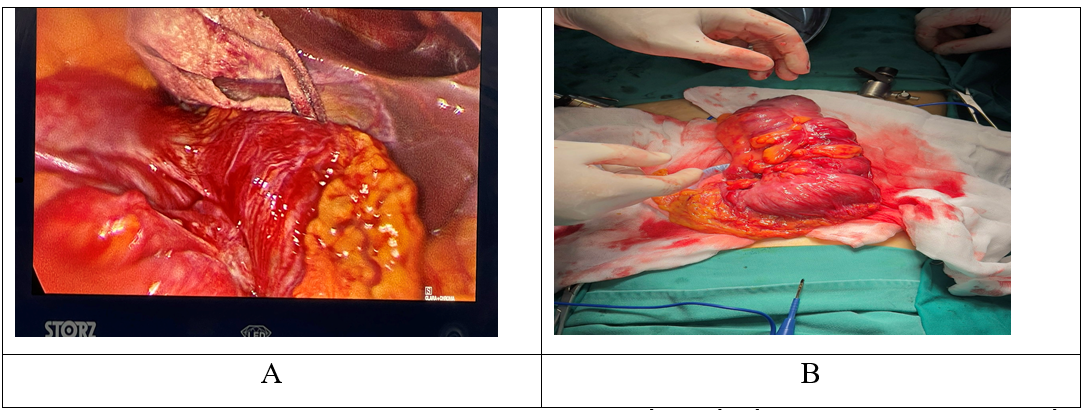

Một bệnh nhân nữ 48 tuổi, khám ở khoa ngoại tổng quát với các triệu chứng đau bụng kéo dài khoảng 2 tuần và trở nặng hơn trong 2 ngày gần đây. Đau bụng âm ỉ có lúc trội thành cơn ở vùng thượng vị và hạ sườn phải, đặc biệt là hạ sườn bên phải kèm theo đi ngoài phân lỏng. Ngoài đau bụng, không có bất kỳ triệu chứng đáng kể nào khác (buồn nôn, nôn, tiểu khó, v.v.). Khám cho thấy huyết áp, mạch và nhiệt độ cơ thể bình thường, bụng chướng nhẹ. Có cảm giác đau ở hạ sườn phải, tuy nhiên, không có phản ứng dội và âm thanh ruột bình thường. Khám tim và phổi không phát hiện bất thường. Số lượng bạch cầu (8.4G/L), hemoglobin, chỉ số hematocrit, CRP (6.52mg/L) và tất cả các thông số sinh hóa khác đều nằm trong giới hạn bình thường. Siêu âm ổ bụng cho thấy hình ảnh khối lồng ruột ở góc hạ sườn phải và một khối tăng âm ở cạnh khối lồng có liên quan đến đoạn này ở giữa ổ bụng nghĩ đến khối u mỡ (Hình 1). Sau khi phát hiện ra điều này, đã đề nghị tiến hành chụp cắt lớp vi tính có cản quang tĩnh mạch. Quan sát thấy khối lồng ở vùng bụng trên bằng chụp CLVT thấy đại tràng lên chui vào đại tràng ngang. Vị trí lồng ruột phát hiện có một khối tỷ trọng mỡ, kích thước đo được là 40x53x55 mm (Hình 2). Với chẩn đoán lồng ruột đại tràng do khối u mỡ, bệnh nhân đã được phẫu thuật cấp cứu. Không có dịch tự do trong khoang bụng trong quá trình phẫu thuật. Phát hiện khối lồng ruột đại tràng ở đại tràng ngang và lòng đại tràng bị hẹp nhiều. Tiến hành gỡ khối lồng ruột và tìm nguyên nhân lồng, nhưng không được. Với tổn thương này, phẫu thuật viên đã cắt bỏ một nửa đại tràng phải và nối hồi – đại tràng.(Hình 3). Trong mô tả của giải phẫu bệnh: đoạn đại tràng đã cắt bỏ, tổn thương được chẩn đoán là u mỡ dưới niêm mạc đại tràng. Không phát hiện bất kỳ bệnh lý nào khác qua quan sát và thăm khám ở các cơ quan khác trong ổ bụng trong trường phẫu thuật.

Hình 3.

(A) trong quá trình phẫu thuật, người ta quan sát thấy khối lồng ruột; (B) hình ảnh cắt bỏ nửa đại tràng phải.